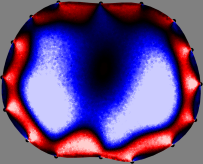

Refer to caption

Figure 2: Fidelity-embedded regularization method. (Left bottom) Correlations between four different column vectors (𝐒ksubscript𝐒𝑘{\bf S}_{k}) and all the remaining column vectors (𝐒subscript𝐒{\bf S}_{\ell}) are visualized. (Right bottom) Performances of the proposed fidelity-embedded regularization method for λ=𝜆\lambda=\infty are shown by numerical simulations.

To explain the FER method, we closely examine the correlations among column vectors of the sensitivity matrix 𝕊𝕊\mathbb{S}, described in Fig. 2. The correlation between 𝐒ksubscript𝐒𝑘{\bf S}_{k} and 𝐒subscript𝐒{\bf S}_{\ell} can be expressed as

for i=1,,16𝑖116i=1,\cdots,16[23]. This shows that the column vector 𝐒ksubscript𝐒𝑘{\bf S}_{k} is like an EEG (electroencephalography) data induced by dipole sources with directions uj,j=1,,16formulae-sequencesubscript𝑢𝑗𝑗116\nabla u_{j},j=1,\cdots,16 at locations ΔksubscriptΔ𝑘\Delta_{k}. Given that two dipole sources at distant locations produce mutually independent data, the correlation between 𝐒ksubscript𝐒𝑘\mathbf{S}_{k} and 𝐒subscript𝐒\mathbf{S}_{\ell} decreases with the distance between ΔksubscriptΔ𝑘\Delta_{k} and ΔsubscriptΔ\Delta_{\ell}. Fig. 2 shows a few images of the correlation 𝐒k,𝐒(|𝐒k||𝐒|)1subscript𝐒𝑘subscript𝐒superscriptsubscript𝐒𝑘subscript𝐒1\left\langle\mathbf{S}_{k},\mathbf{S}_{\ell}\right\rangle(|\mathbf{S}_{k}||\mathbf{S}_{\ell}|)^{-1} as a function of \ell for four different positions ΔksubscriptΔ𝑘\Delta_{k}. The correlation decreases rapidly as the distance increases. In the green regions where the correlation is almost zero, 𝐒subscript𝐒{\bf S}_{\ell} is nearly orthogonal to 𝐒ksubscript𝐒𝑘{\bf S}_{k}.